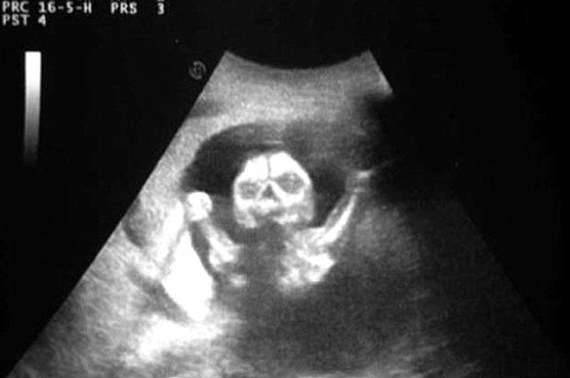

▼看到肚子里宝宝这一幕,想必会吓一跳。胎儿正把双手举向上方,感觉随时会蹦出来一样,头部的模样也让人超不安的!